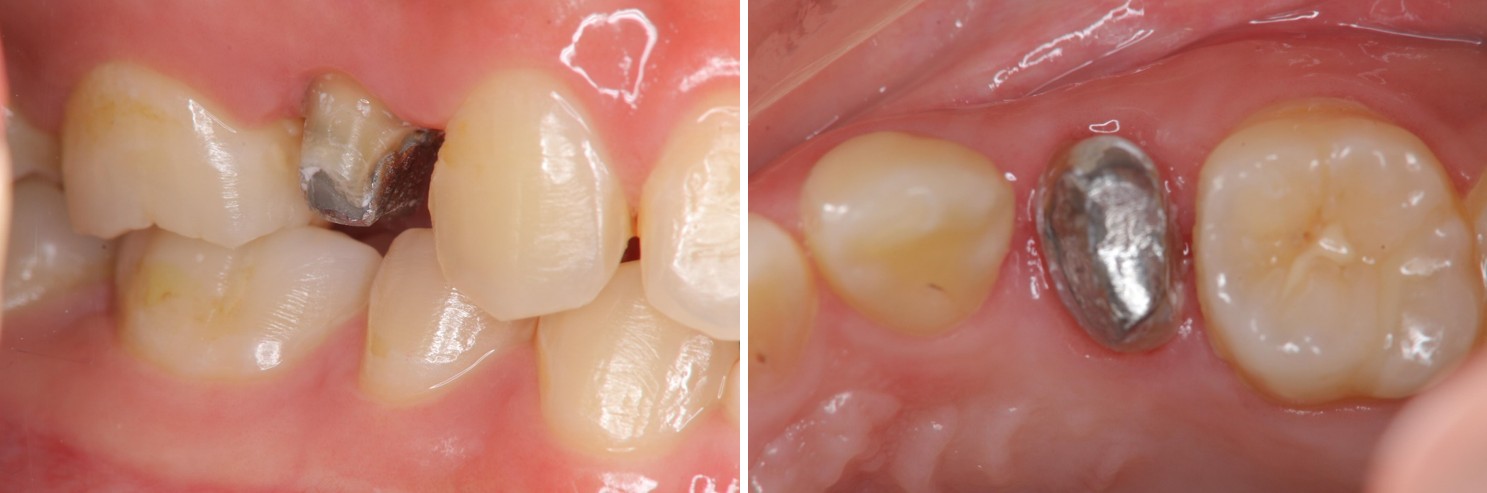

膺復前評估牙齦、牙齒狀態

治療後,牙周咬合良好

治療後,密合度良好

術前、術後比較